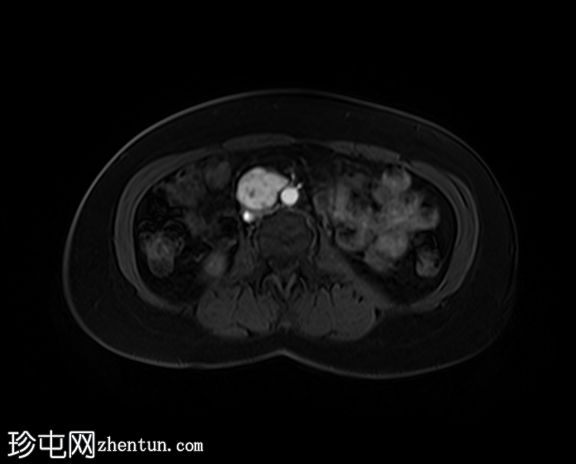

轴位T2加权像

脂肪抑制像

右侧腹膜后可见一边界清晰的肿块,位于主动脉分叉上方。

病灶大小约为3.5 x 3.0 x 4.1 cm(前后径 x 横径 x 头尾径)。

T2加权像显示异质性高信号,DWI/ADC显示明显扩散受限,增强后明显强化。

对下腔静脉有轻微压迫,无直接侵犯或血栓形成的证据。

病灶旁可见两个小的、不规则的淋巴结,疑似转移。